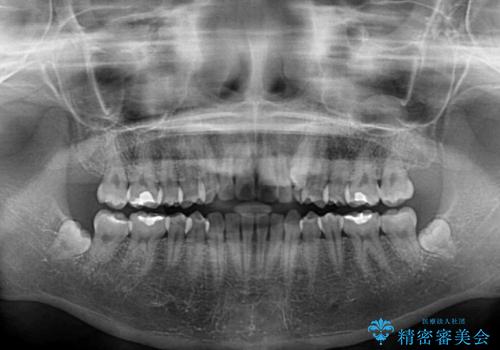

気になる残存乳歯と八重歯 ワイヤー矯正を併用したインビザライン治療

- 八重歯を気にして来院された患者様です。

八重歯のために乳歯が残存していたため、乳歯を抜去して八重歯となっている犬歯を歯列に収めることとしました。

八重歯の移動量が多くなるため、インビザラインと併用してワイヤー矯正を行い、八重歯を改善した後に、上下歯列をインビザラインで整えることとしました。

犬歯は歯根が長くて太いため移動に時間がかかる上に、周囲の歯が八重歯に寄ってきてしまうため、仕上がるまでに期間がかかりました。